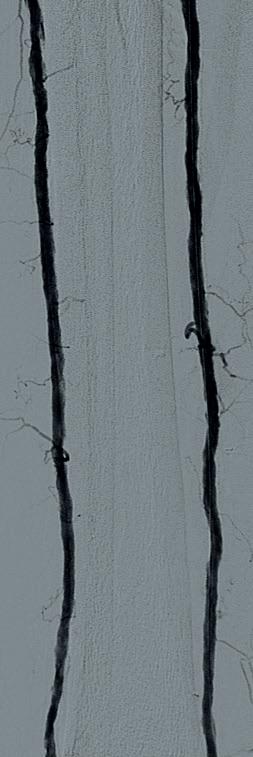

Ultrasound-guided access was obtained in the left common femoral artery and right lower extremity angiography confirmed nonobstructive inflow disease with tandem calcified 70 and 80% P1 as well as P2 extending into P3 disease. The anterior tibial

artery was noted to have a highgrade stenosis proximally with severe diffuse disease throughout its course, with essentially calcified occlusive disease distally with diffuse disease of the dorsalis pedis artery. The TP trunk was occluded proximally with complete occlusions of the TP trunk peroneal and posterior tibial vessels, with reconstitution of the posterior tibial artery above the ankle via geniculate collaterals. There was moderate diffuse disease of the plantar vessels as well (Figure 2a–c).

A 6F Ansel sheath (Cook Medical) was placed in the right CFA, and the anterior tibial occlusion was crossed with an Abbott Command 0.014” wire, followed by treatment of the popliteal lesions with a 6.0x60mm IVL catheter followed by drugcoated balloon (DCB) angioplasty with a Bard 6x150 Lutonix balloon, with reduction to a <30% residual. The right anterior tibial artery was treated with a 3.5x60mm

IVL catheter along a ~20cm segment of the lesion, followed by percutaneous transluminal angioplasty (PTA) with a 3x3.5x210mm Nanocross balloon (Medtronic), with an excellent result without recoil, despite the heavy calcific burden of disease. Antegrade traversal of the TP trunk and posterior tibial arteries was unsuccessful despite an escalating wire strategy, so

the posterior tibial artery was accessed in a retrograde manner with ultrasound guidance. The 0.014” Abbott Command wire was eventually delivered to the common femoral artery using a Quick-Cross 0.014” support catheter (Spectranetics) and exteriorised using a 7mm goose neck snare (Microvena). IVL of the TP trunk and proximal posterior (approximately 20cm of treatment length) tibial artery was performed with a 3.5x40 S4 IVL catheter in less than five minutes. This was followed by PTA distally with a tapered 3x3.5x210mm Nanocross balloon. A 4x38mm Medtronic Resolute Onyx DES was placed to treat a residual dissection in the TP trunk with final angiography demonstrating three-vessel runoff to the foot (Figure 3a–c). Remarkably, the anterior tibial IVL/PTA result showed no appreciable recoil, despite the fact that it took over 90 minutes to complete the TP trunk and posterior tibial reconstruction. He was discharged later that day. He later underwent second toe amputation and successfully healed his wounds.

Figure 3a Figure 3b Figure 3c